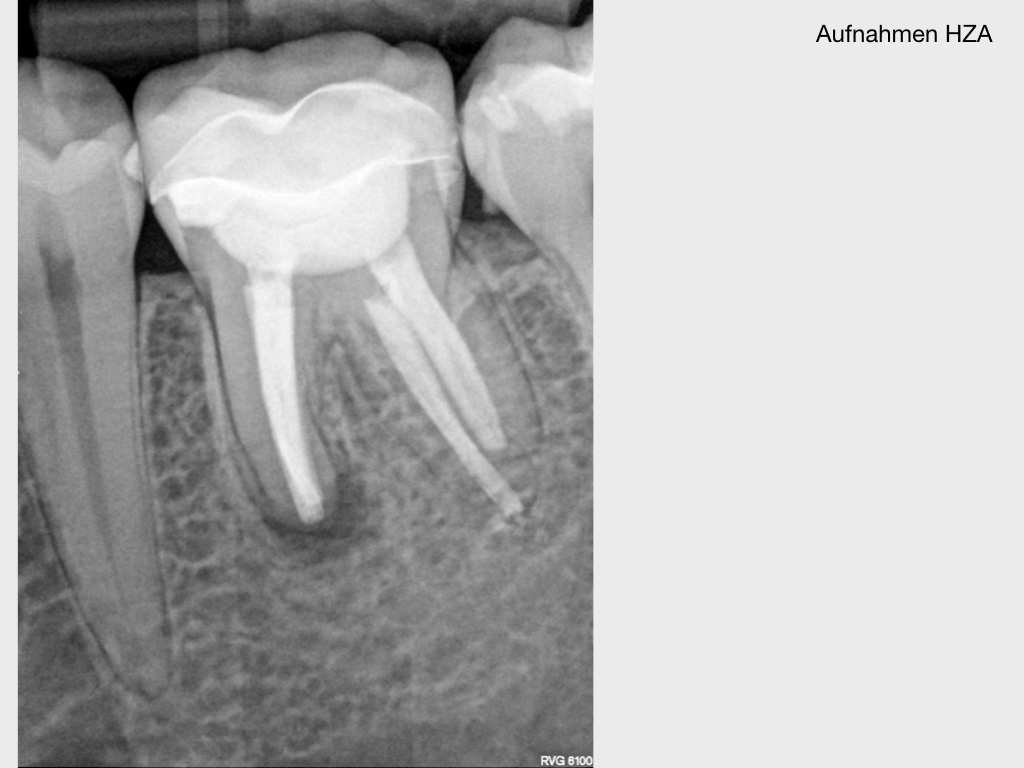

WSR2.001 Veröffentlicht 2. März 2020 am 1024 × 768 in Kurz berichtet – Z.n. WSR – Revision mit minimalinvasivem Zugang